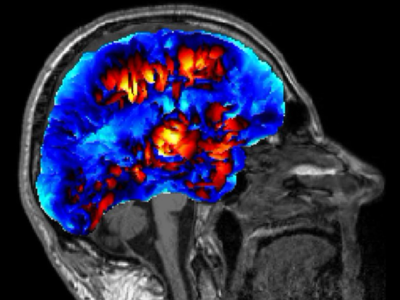

No 1 | Planifier la résection d’une tumeur cérébrale à l’aide des circuits cérébraux